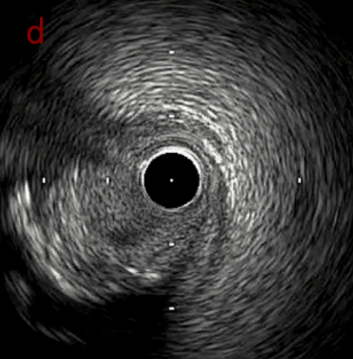

IVUS after OAS high speed 3回

IVUS imaging after high speed 3回

a,b,cはさらに石灰化に食い込み、石灰化量は減少。

それに伴いdではbiasがさらにtentingのIVUS所見にへんかしhigh injury riskと思われた。

引き続き造影で確認してpinpointで引きのOAS high speedを3回さらに追加のためcでIVUSマーキングを行い、その点より引きで赤線のpinpoint OAS high speedを行い、dに関してはinjury回避のためにOASを当てない方針とした。

IVUS after OAS high speed 3回追加

IVUS imaging after high speed 3回追加

a,b,cの十分な石灰化のsanding。

High riskのbias所見へと変わっていったdの部位に関してはpinpoint OASを行うことでinjuryなく治療できた。